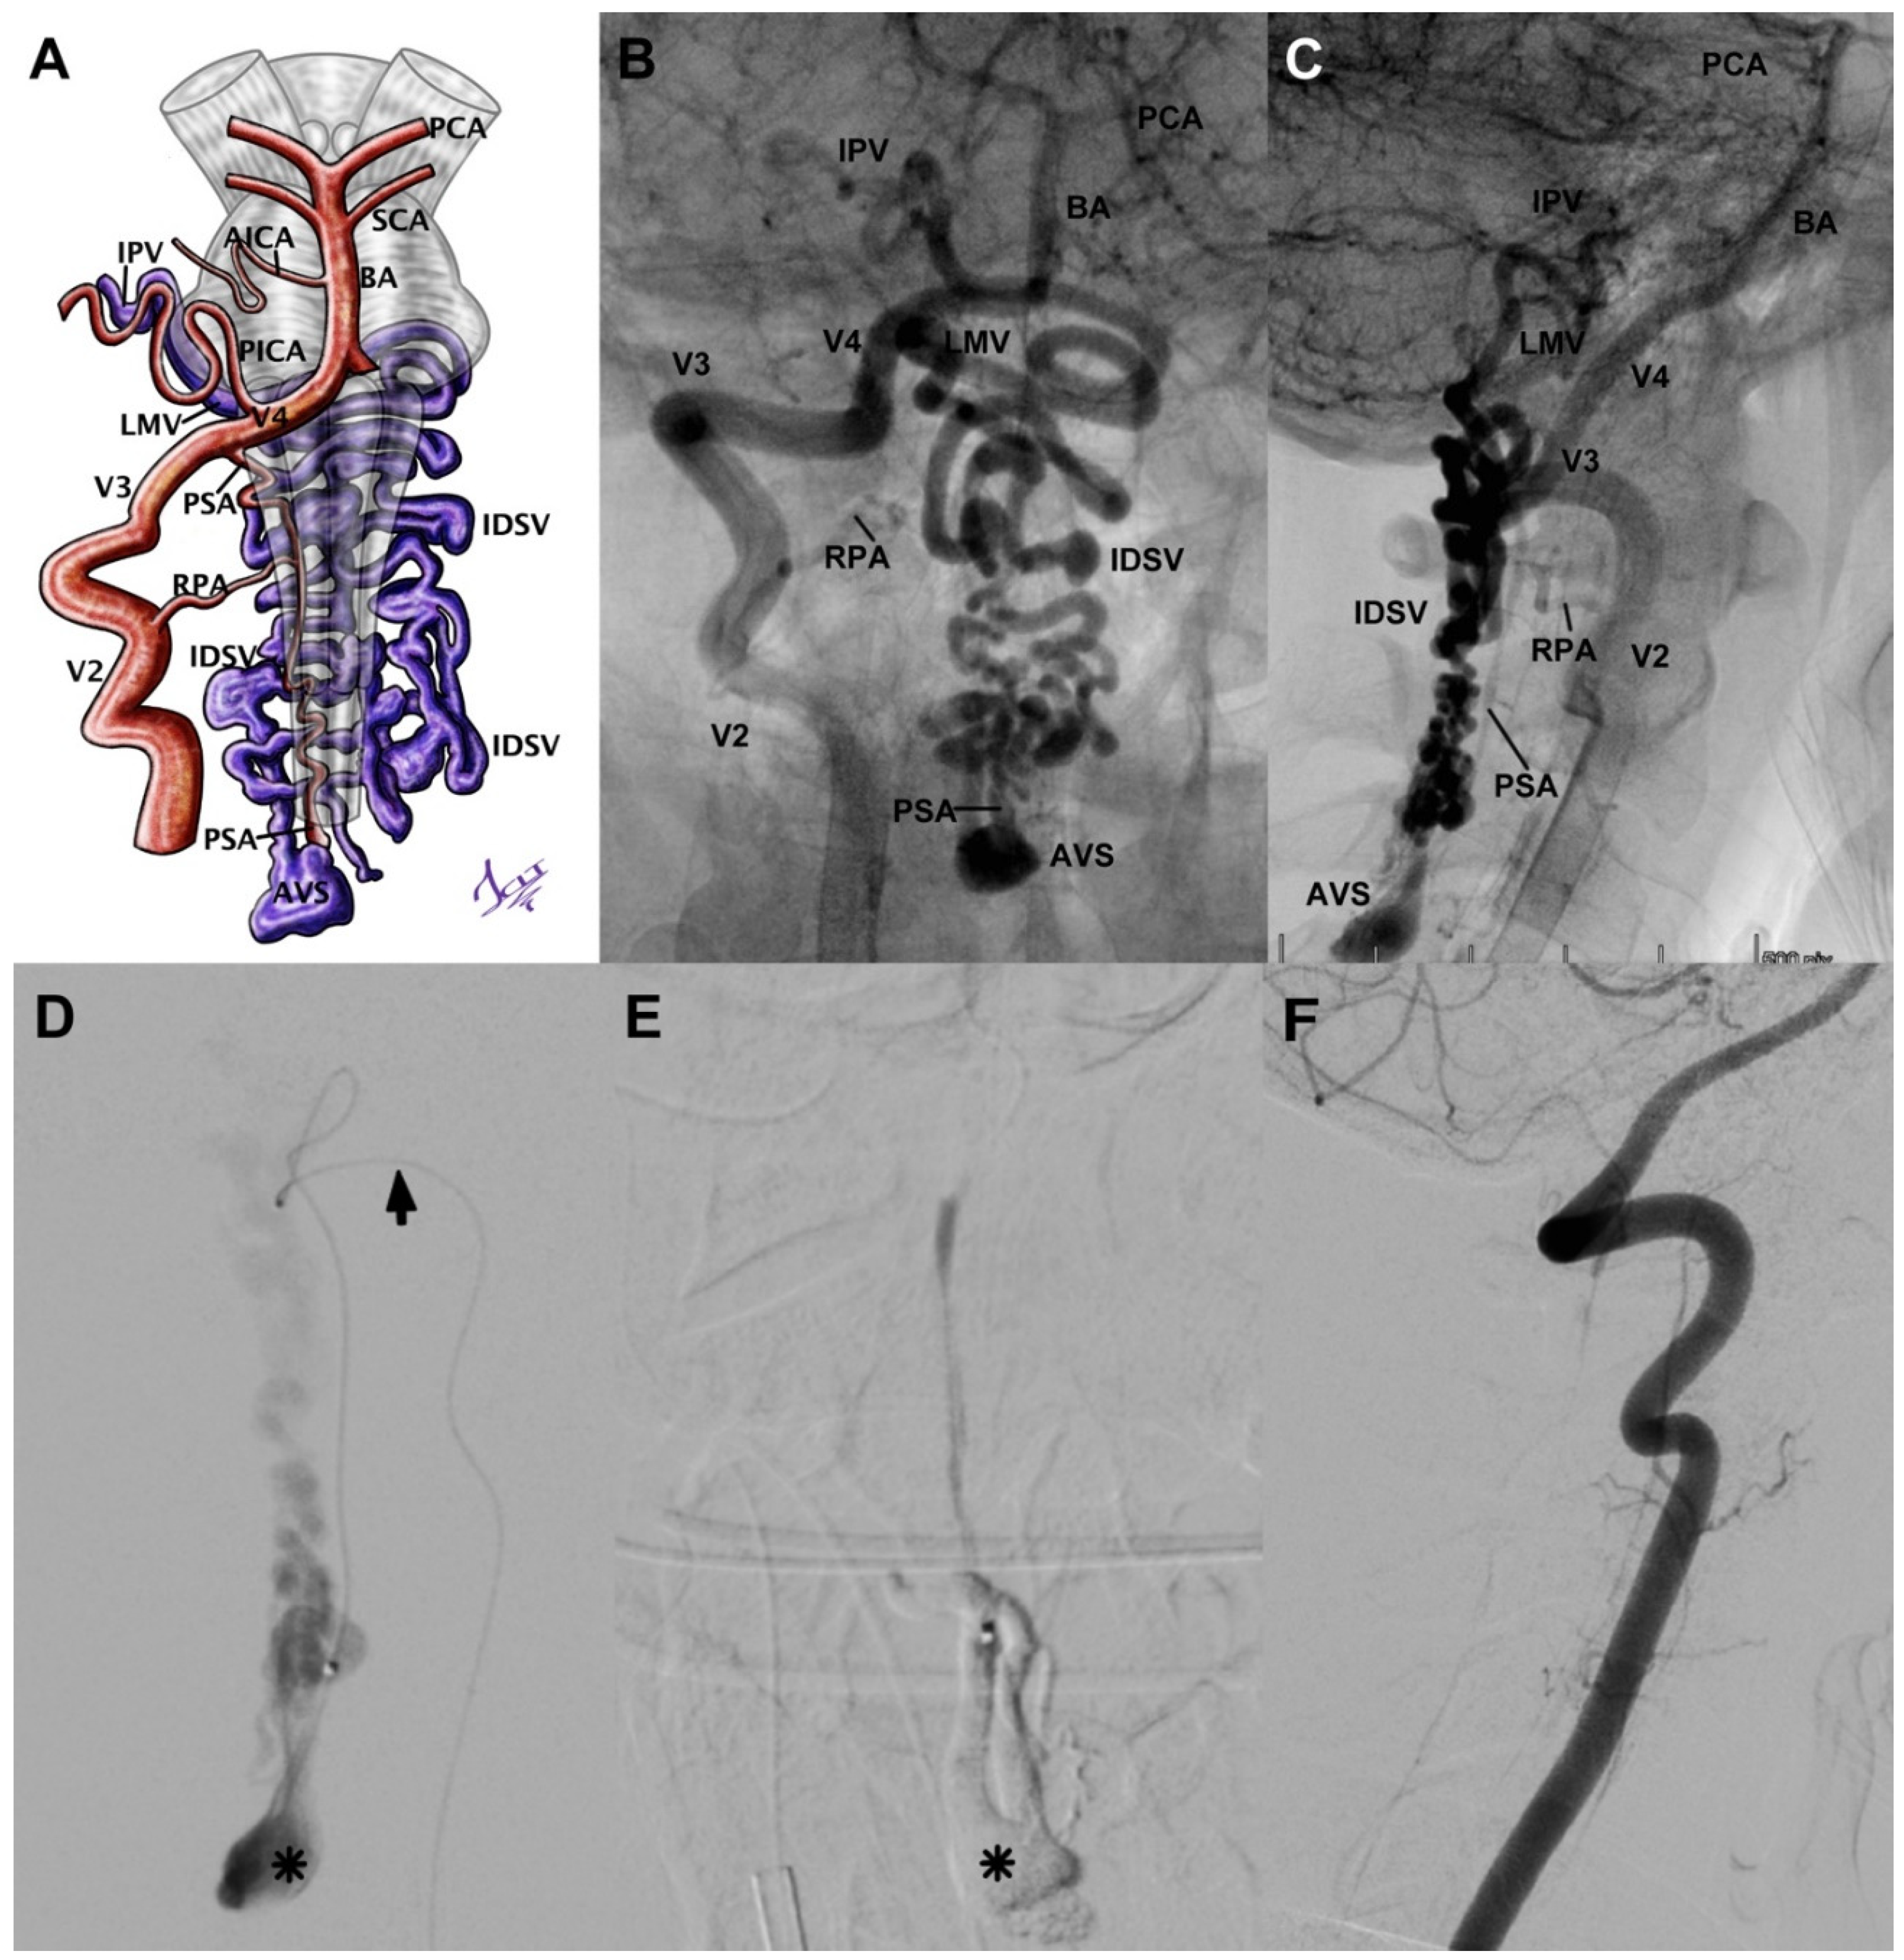

3.5.2. Case 7

| Case 7 | 15/F | SAH Fisher IV, headache, neck stiffness | 3 | Type V dorsal CCJ AVF (Hiramatsu) | Posterior spinal artery | Middle ostium at C3 | Venous aneurysm | Venous drainage to intradural varicose veins–inferior petrous vein | Embolized with Histoacryl | Complete occlusion, without neurological deficit | 0 |